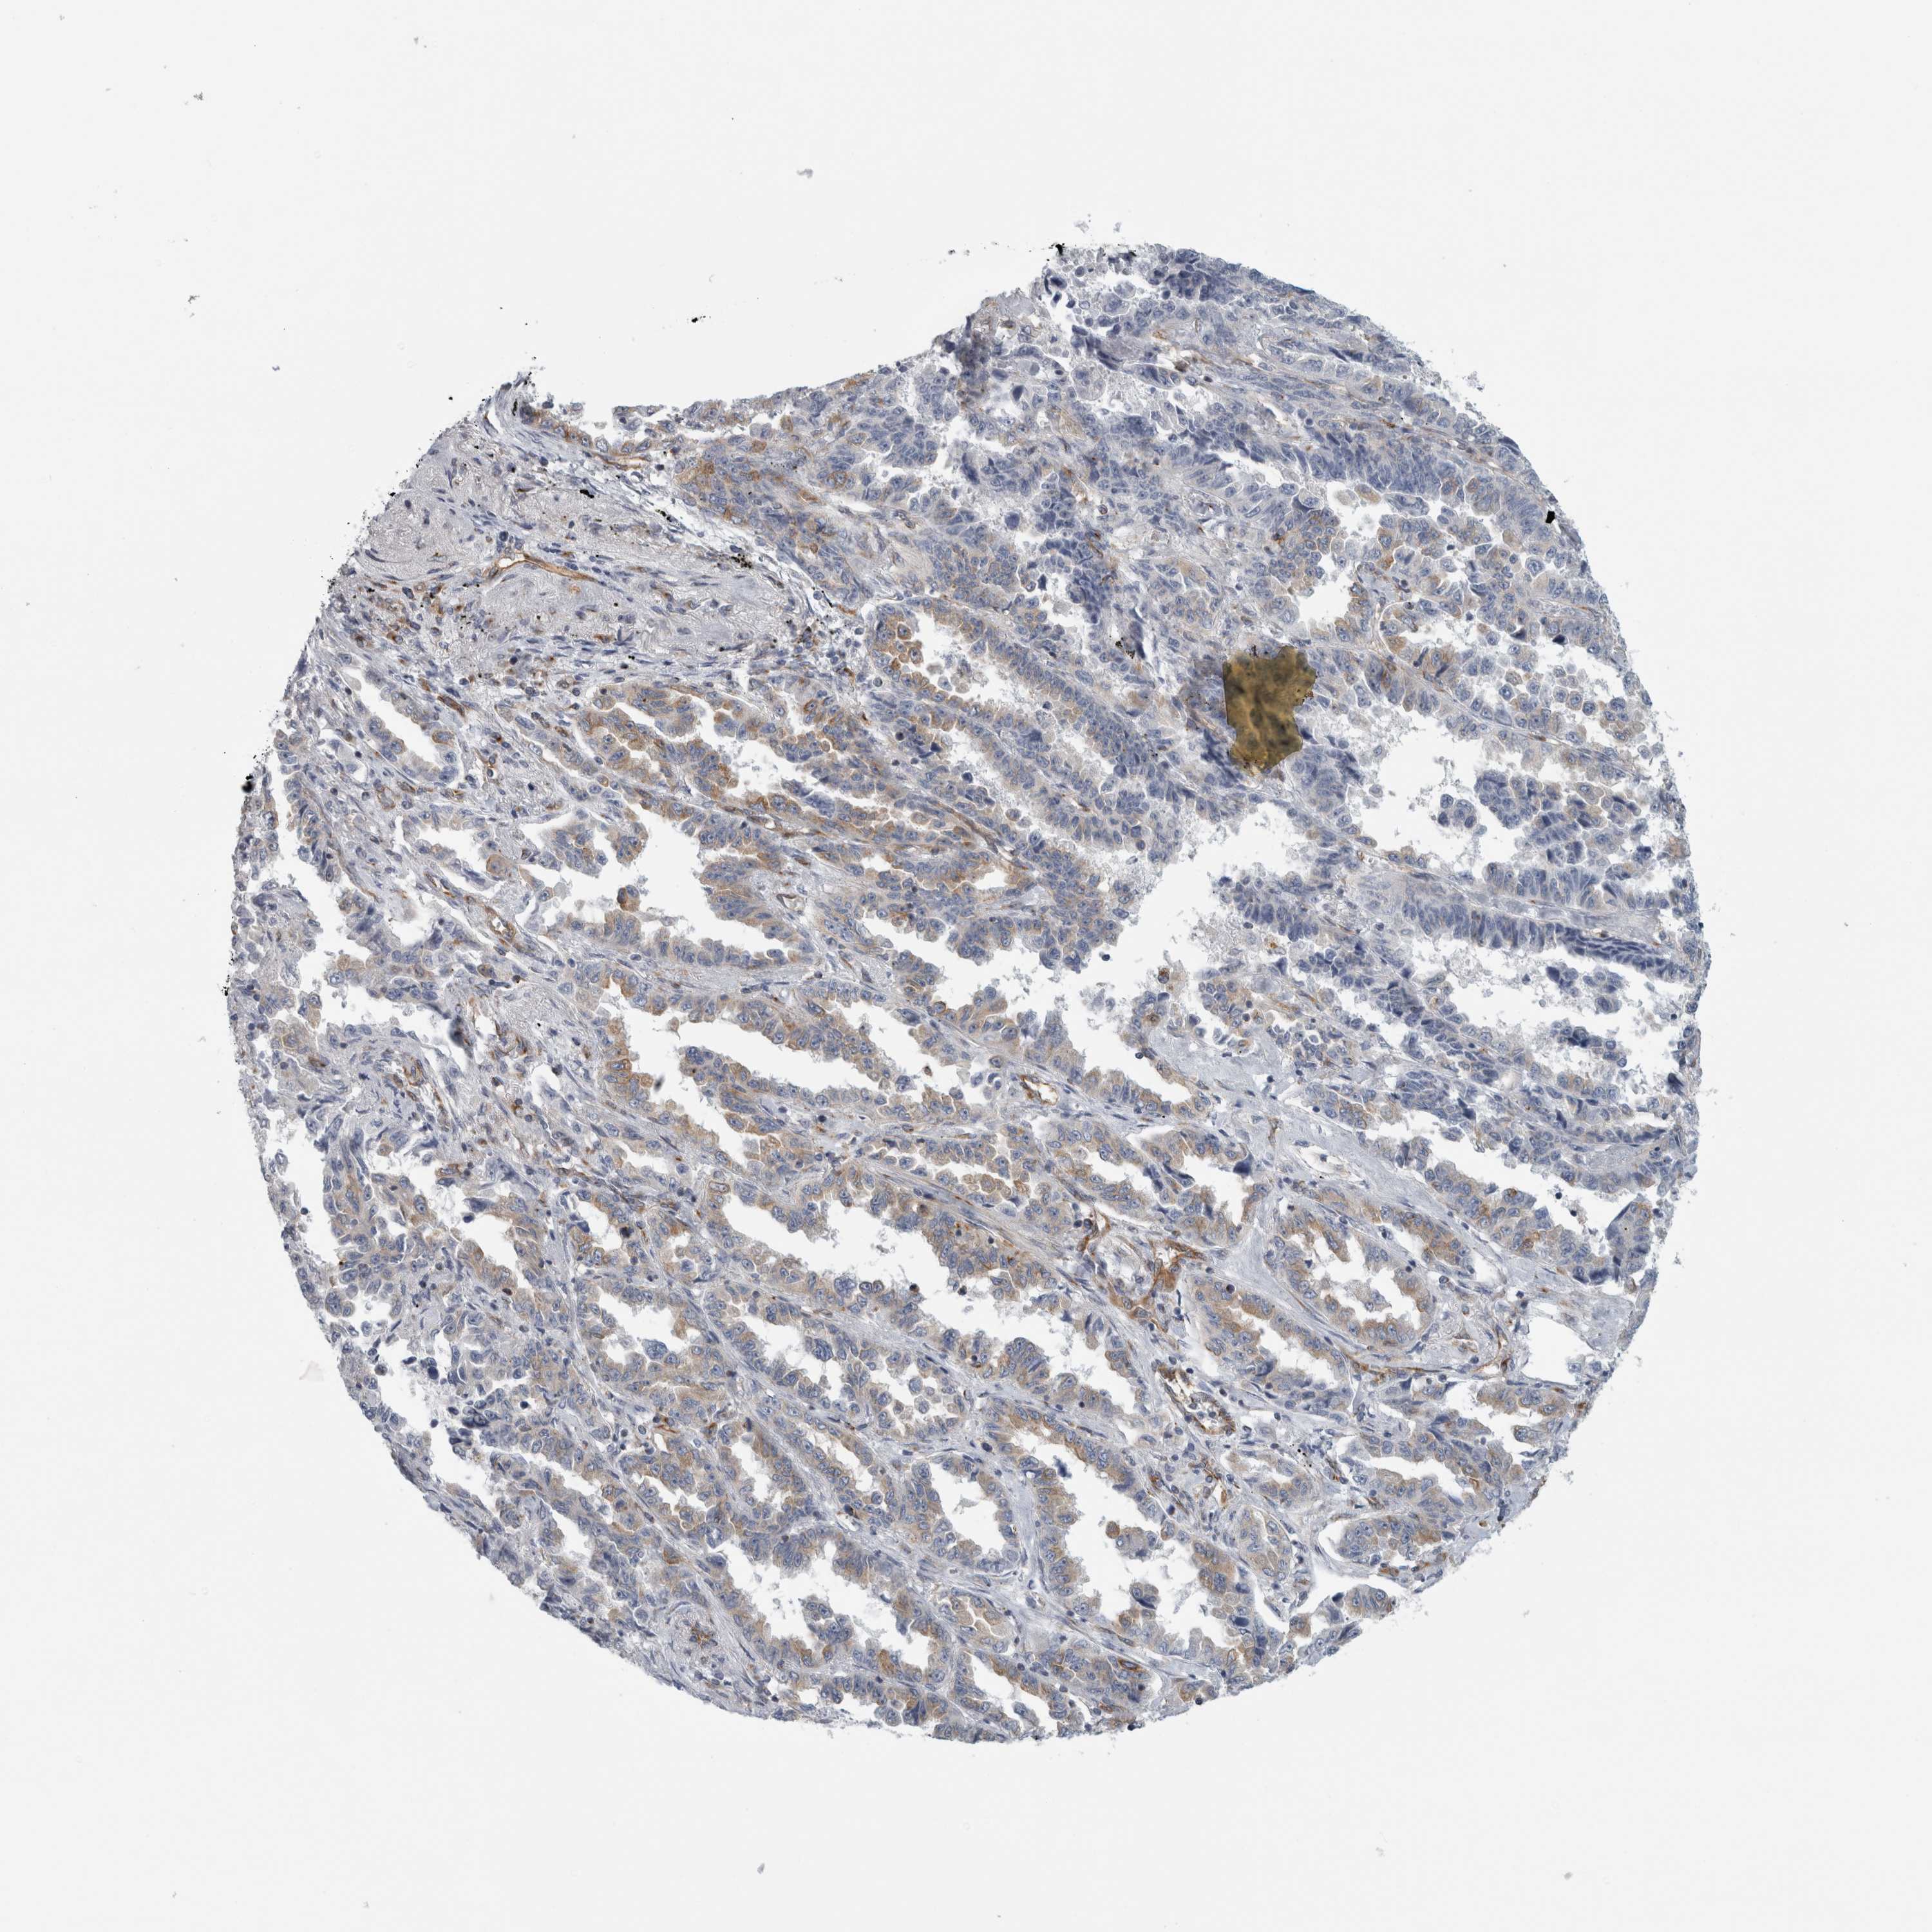

CANCER LUNG CANCER Show tissue menu

LUAD TCGA LUAD VALIDATION LUSC TCGA LUSC VALIDATION PROTEIN LUAD CPTAC PROTEIN LUSC CPTAC PROTEIN EXPRESSION